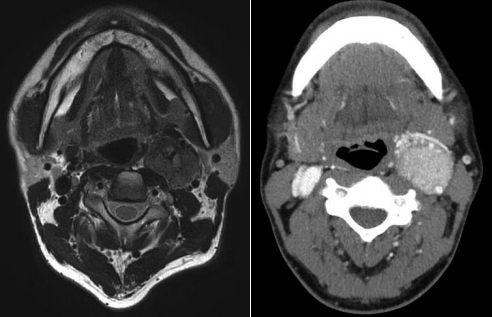

44세 남자 환자가 좌측 경부에 서서히 자라는 박동성 무통성 종괴를 주소로 내원하였다. 촉진 시 고무를 만지는 듯한 느낌이였고 좌우로 움직이나 상하로 움직이지는 않았다. 시행한 영상 소견이 다음과 같다. 이 질환에 대한 설명 중 맞는 것은?

해 설 위 증례는 경부에 발생하는 박동성 종괴로, 위치상 총경동맥이 분지하는 부위에서 내경동맥과 외경동맥을 분리시키면서 커져있으므로 경동맥소체종양으로 진단할 수 있다. ① Catecholamine을 분비하는 종양인 pheochromocytoma가 동반될 수 있는 thyroid medullary carcinoma의 경우 체크하여야 한다. ② 답가지는 schwannoma에서 보이는 소견이다. ③ 내경동맥을 내측으로 외경동맥은 외측으로 전위시킨다. ⑤ 새열기형낭종이나 갑상설관낭종에 대한 설명이다.